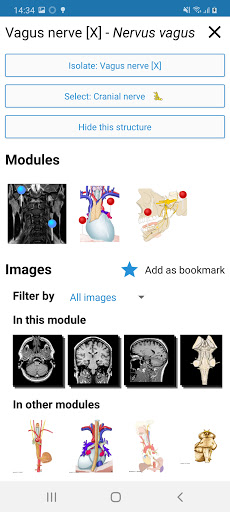

*Vista detallada mejorada de partes anatómicas para una identificación más fácil en imágenes del módulo actual y otros.

*Visibilidad mejorada de las definiciones de partes anatómicas

. *Navegación entre partes anatómicas usando enlaces de descripción.

la vista de detalles de una estructura anatómica ahora se muestran los términos relacionados

-Dentro de la vista de detalles de una estructura anatómica , un alfiler ahora señala la estructura relacionada en todas las imágenes presentes

También toque directamente en la imagen para navegar a la imagen presentada en ese módulo

-Nueva opción para expandir galerías de imágenes en la pantalla de información de estructura anatómica.

- "Filtrar por", en la vista de detalles ahora puede filtrar las imágenes que contienen la estructura anatómica por modalidad

- "Filtrar por", en la vista de detalles ahora puede filtrar las imágenes que contienen la estructura anatómica por modalidad

- Ahora puede ocultar las estructuras una por una (nuevo botón dentro de la ventana emergente de descripción) y visualizarlas nuevamente en el menú derecho